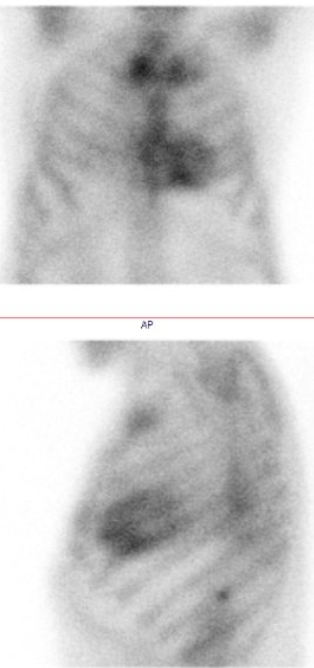

/ Obr. č. 1: Statická scintigrafie hrudníku v přední a levé boční projekci. Vyšetření 3 hodiny po aplikaci radiofarmaka.

Prokazujeme zvýšenou depozici radiofarmaka v myokardu levé srdeční komory s maximem v oblasti septa, vyšší je depozice i v PK. Zvýšená depozice je vyšší než v žebrech - dle semikvantitavní škály jde o stupeň 3. Je vysoká EF LK kolem 70 %.